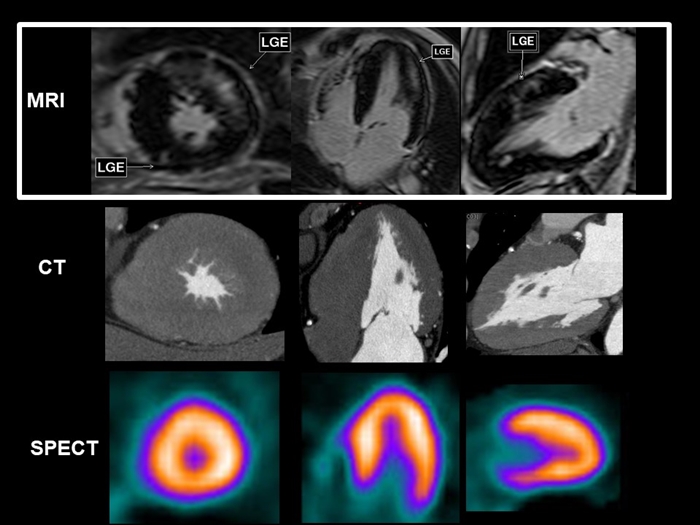

心臓MRIの画像

上の画像で白枠の中の画像が心臓MRIで撮影した心臓の左心室です。

下に同じ人のCTやSPECTなど、他の方法で撮影した左心室の画像を示していますが、

造影剤を使った心臓MRIでは, 他の画像検査では映らない左心室の心筋の病変を映し出しています。

画像の中で白く浮かび上がっているのが心筋症の病変部です。